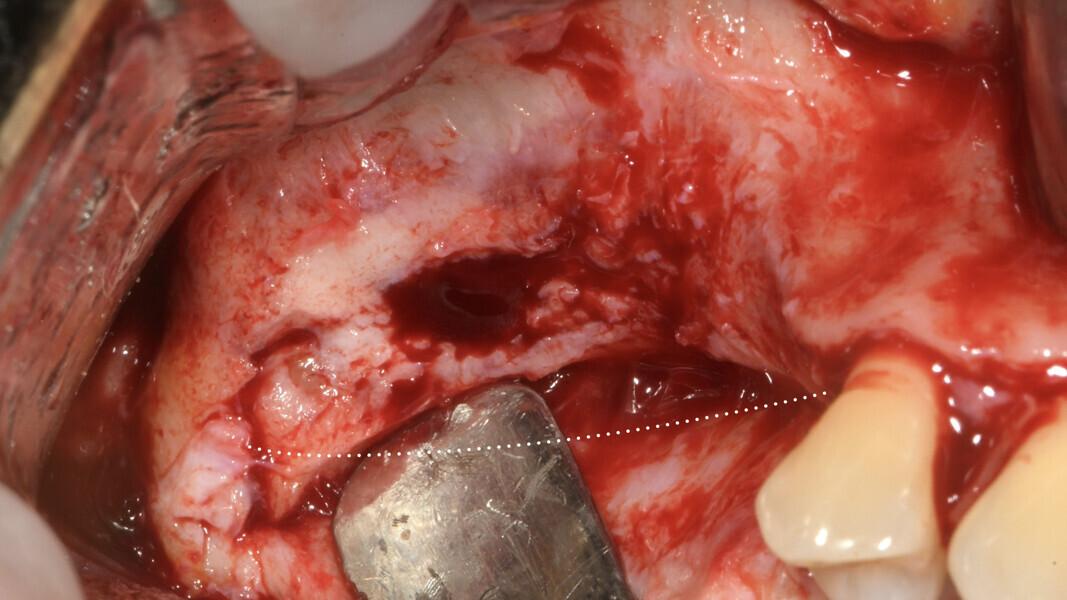

On the day of implant surgery, a para-crestal horizontal incision was made to expose the mesh and remove it, after the removal of the titanium screws and the new bone that had formed over the mesh (Figs. 25a & b, 26). Clinical examination showed complete regeneration of the vertical defect and the absence of pseudo-periosteum or thin pseudo-periosteum (< 1 mm), corresponding to the pseudo-periosteum Type 1 according to the Cucchi classification (Figs. 27 & 28).20